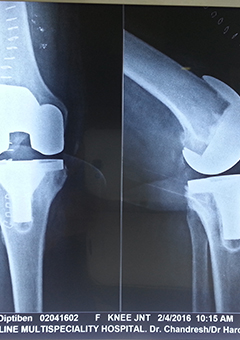

Kesardevi Total Knee Replacement

"Kesardevi, who had a severe knee deformity, underwent a total knee replacement surgery performed by Dr. Chandresh Sharma at Lifeline

Kesardevi